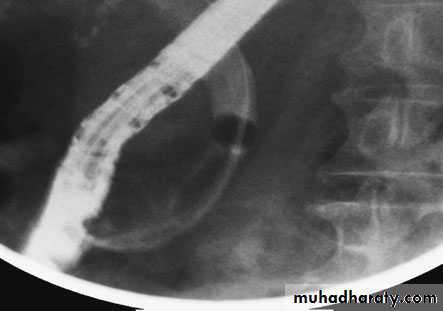

55Endoscopic retrograde cholangiopancreatography: thepatient presented with jaundice 4 days after laparoscopic cholecystectomy.The bile duct contained multiple stones